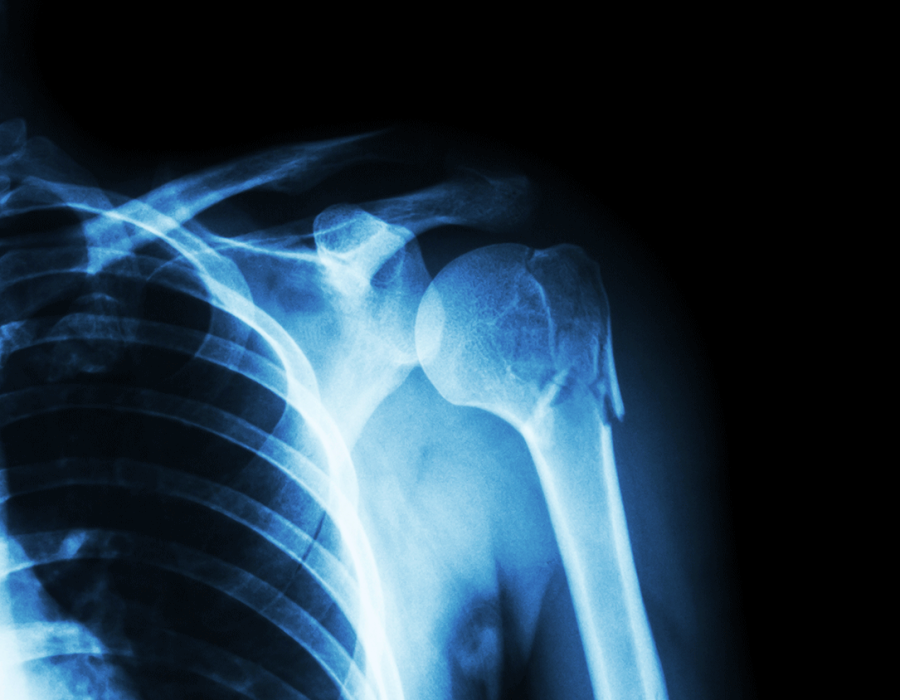

X-ray technicians, also known as radiologic technologists, play a vital role in healthcare by producing images that aid in diagnosing medical conditions. To become an X-ray tech, aspiring students typically enroll in specialized xray tech schools that offer accredited certificate or associate degree programs. These programs combine classroom instruction with hands-on clinical experience, preparing students with the necessary skills to operate imaging equipment and ensure patient safety.